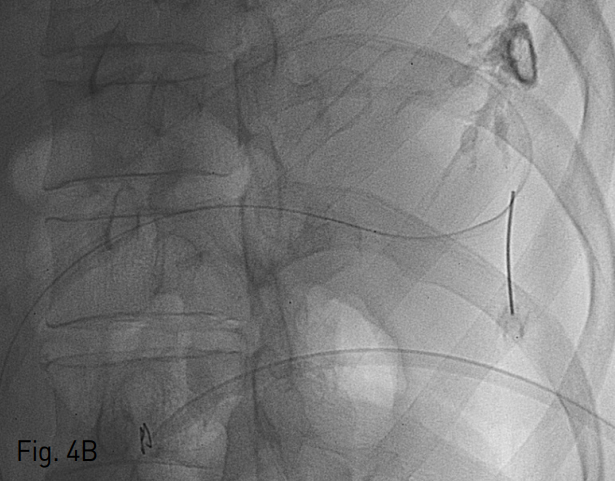

Fig. 4

Ultrasonography and fluoroscopy guided 22 gauge Chiba needle is inserted in to the Jackson Pratt drainage catheter induced maturation tract directly on anteroposterior (A) and right 45 degree oblique (B) fluor oscopy images. Hair wire in the Jack son-Pratt drainage catheter induced matur ation tract on fluoroscopic image (C).